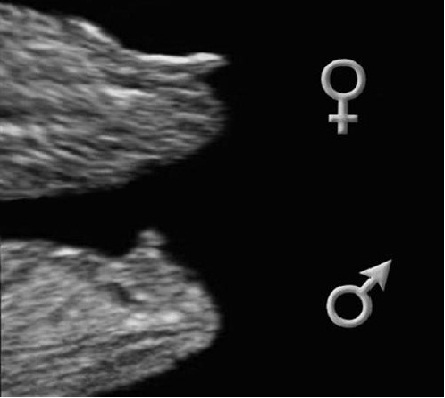

вот как надо определять пол на ранних сроках,конечно погрешность есть.так же как и на любом сроке могут ошибаться)просто я часто видела снимки девочек где между ног врач узист пытается что то увидеть и предположить-вот тогда они часто и ошибаются

я ходила ровно в 12. Но у нас опережение на неделю и нам предположили мальчика! Посмотрим как дальше будет, надеюсь не ошиблись!